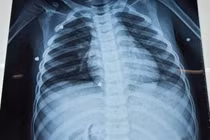

Ảnh minh họa/ nguồn sggp.org.vn